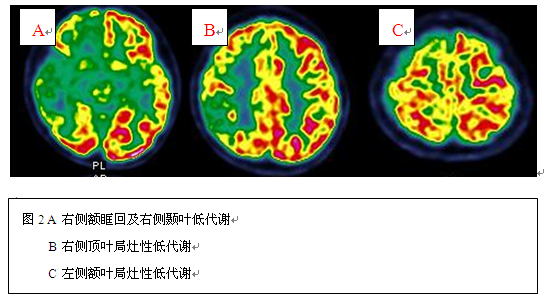

辅助检查:头颅MR示右侧额底、左侧额叶、右侧颞叶内侧多发异常信号影(具体见图1)。头颅CT示室管膜下钙化结节影。PET示右侧额叶底面、右侧颞叶及右侧顶叶多发低代谢区(见图2);VEEG示发作间期各脑区见癫痫样放电,以右侧前头部著;发作期为右侧前头部起源的部分性发作(见图3)。心脏彩超、腹部彩超:无异常。韦氏智力测试:言语智商50,操作智商57,全量表智商49;韦氏记忆测试:9分。